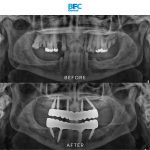

เคสรากเทียมทั้งปาก

รากเทียมทั้งปากด้วยระบบ Digital พร้อมมีฟันใหม่ได้ภายใน 1 วัน